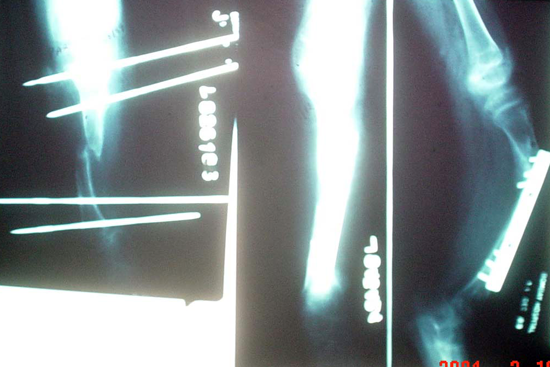

Limb Lengthening